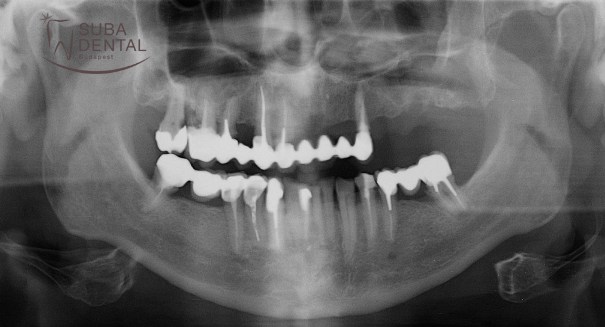

Panoramic radiograph of the initial condition. Several teeth were beyond repair, with all upper teeth due for removal

After 3 months of healing the CT scan revealed that bone height was inadequate on both sides, and a sinus lift was necessary, which could not be performed in the same sitting with implant surgery due to inadequate bone height. In the second sitting bone graft was performed in the upper arch and the lower implants were installed (2 per quadrant).